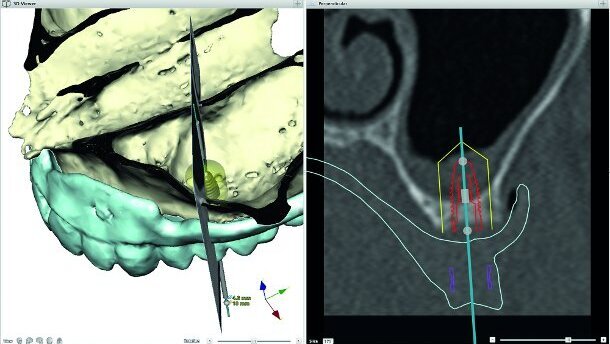

In dental medicine, computer technology is no more a real technological revolution. Virtual implant-planning based on volume tomography has facilitated the decision making and information for a patient for quite some time now (Fig. 1). Computer-assisted implant placing occurs with high precision in partially or fully edentulous patients.[1] Here, the so-called backward planning ensures a high level of predictability of the surgical and prosthetic result. The surgical realisation of the 3-D planning with stereolithographic splints is an important advancement in complex cases and can contribute to less invasive and rapid proceedings in selected cases. By this, one can precisely determine whether a completely “flapless” procedure is possible for single or all planned implants in the jaw and which augmentative technique is indicated.[2] Especially for older patients with relatively more risks when implanting, a well-planned, minimally-invasive proceeding with a shortened operation time is of advantage.[3, 4]